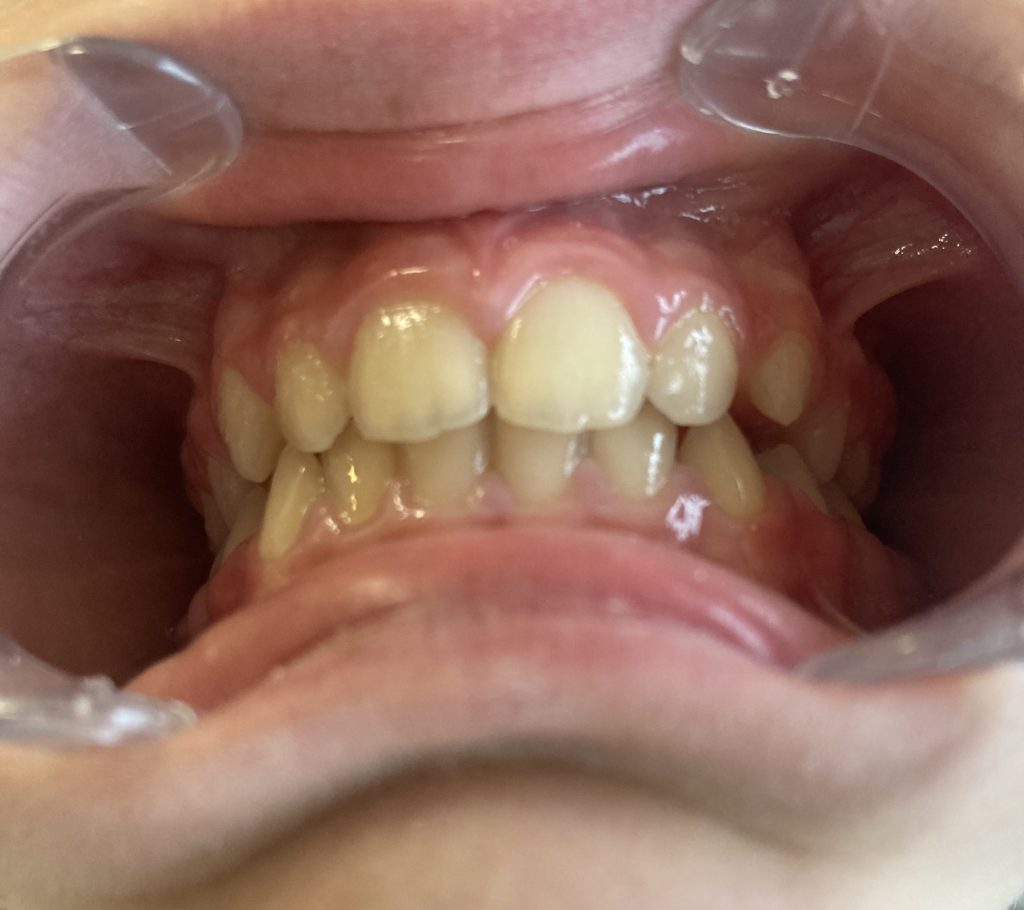

Découvrez en images l’évolution d’une béance liée à une dyspraxie linguale et les bénéfices apportés par une prise en charge adaptée.